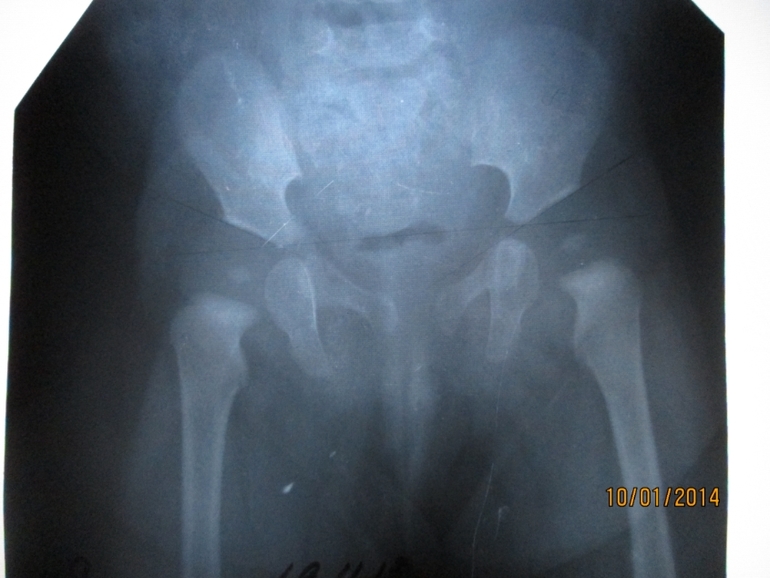

Результат рентгена в 5,5 мес.: объем мягких тканей не увеличен. Костная структура равномерная, трабекулярное строение сохранено. Наружные контуры кости (с учетом анатомических особенностей) – ровные четкие. Кортикальный слой не изменен. Форма ростковых зон соответствует возрасту. Рентгеновские суставные щели симметричны. Конгруэнтность суставных впадин и суставных головок сохранена, развитие точек окостенения головок симметричное, соответствует возрасту. Ацетабулярные углы в пределах нормы – справа 28°, слева 28°. Положение центрации головок не изменены. Линии Шентона ровные, не прерываются. Снимок прилагается!

Но, ортопеду снимок не понравился говорит, что есть децентрация головок и углы немного не такие какие нужно. Возможно ли, что ребенок просто не правильно лежал по время рентгена?